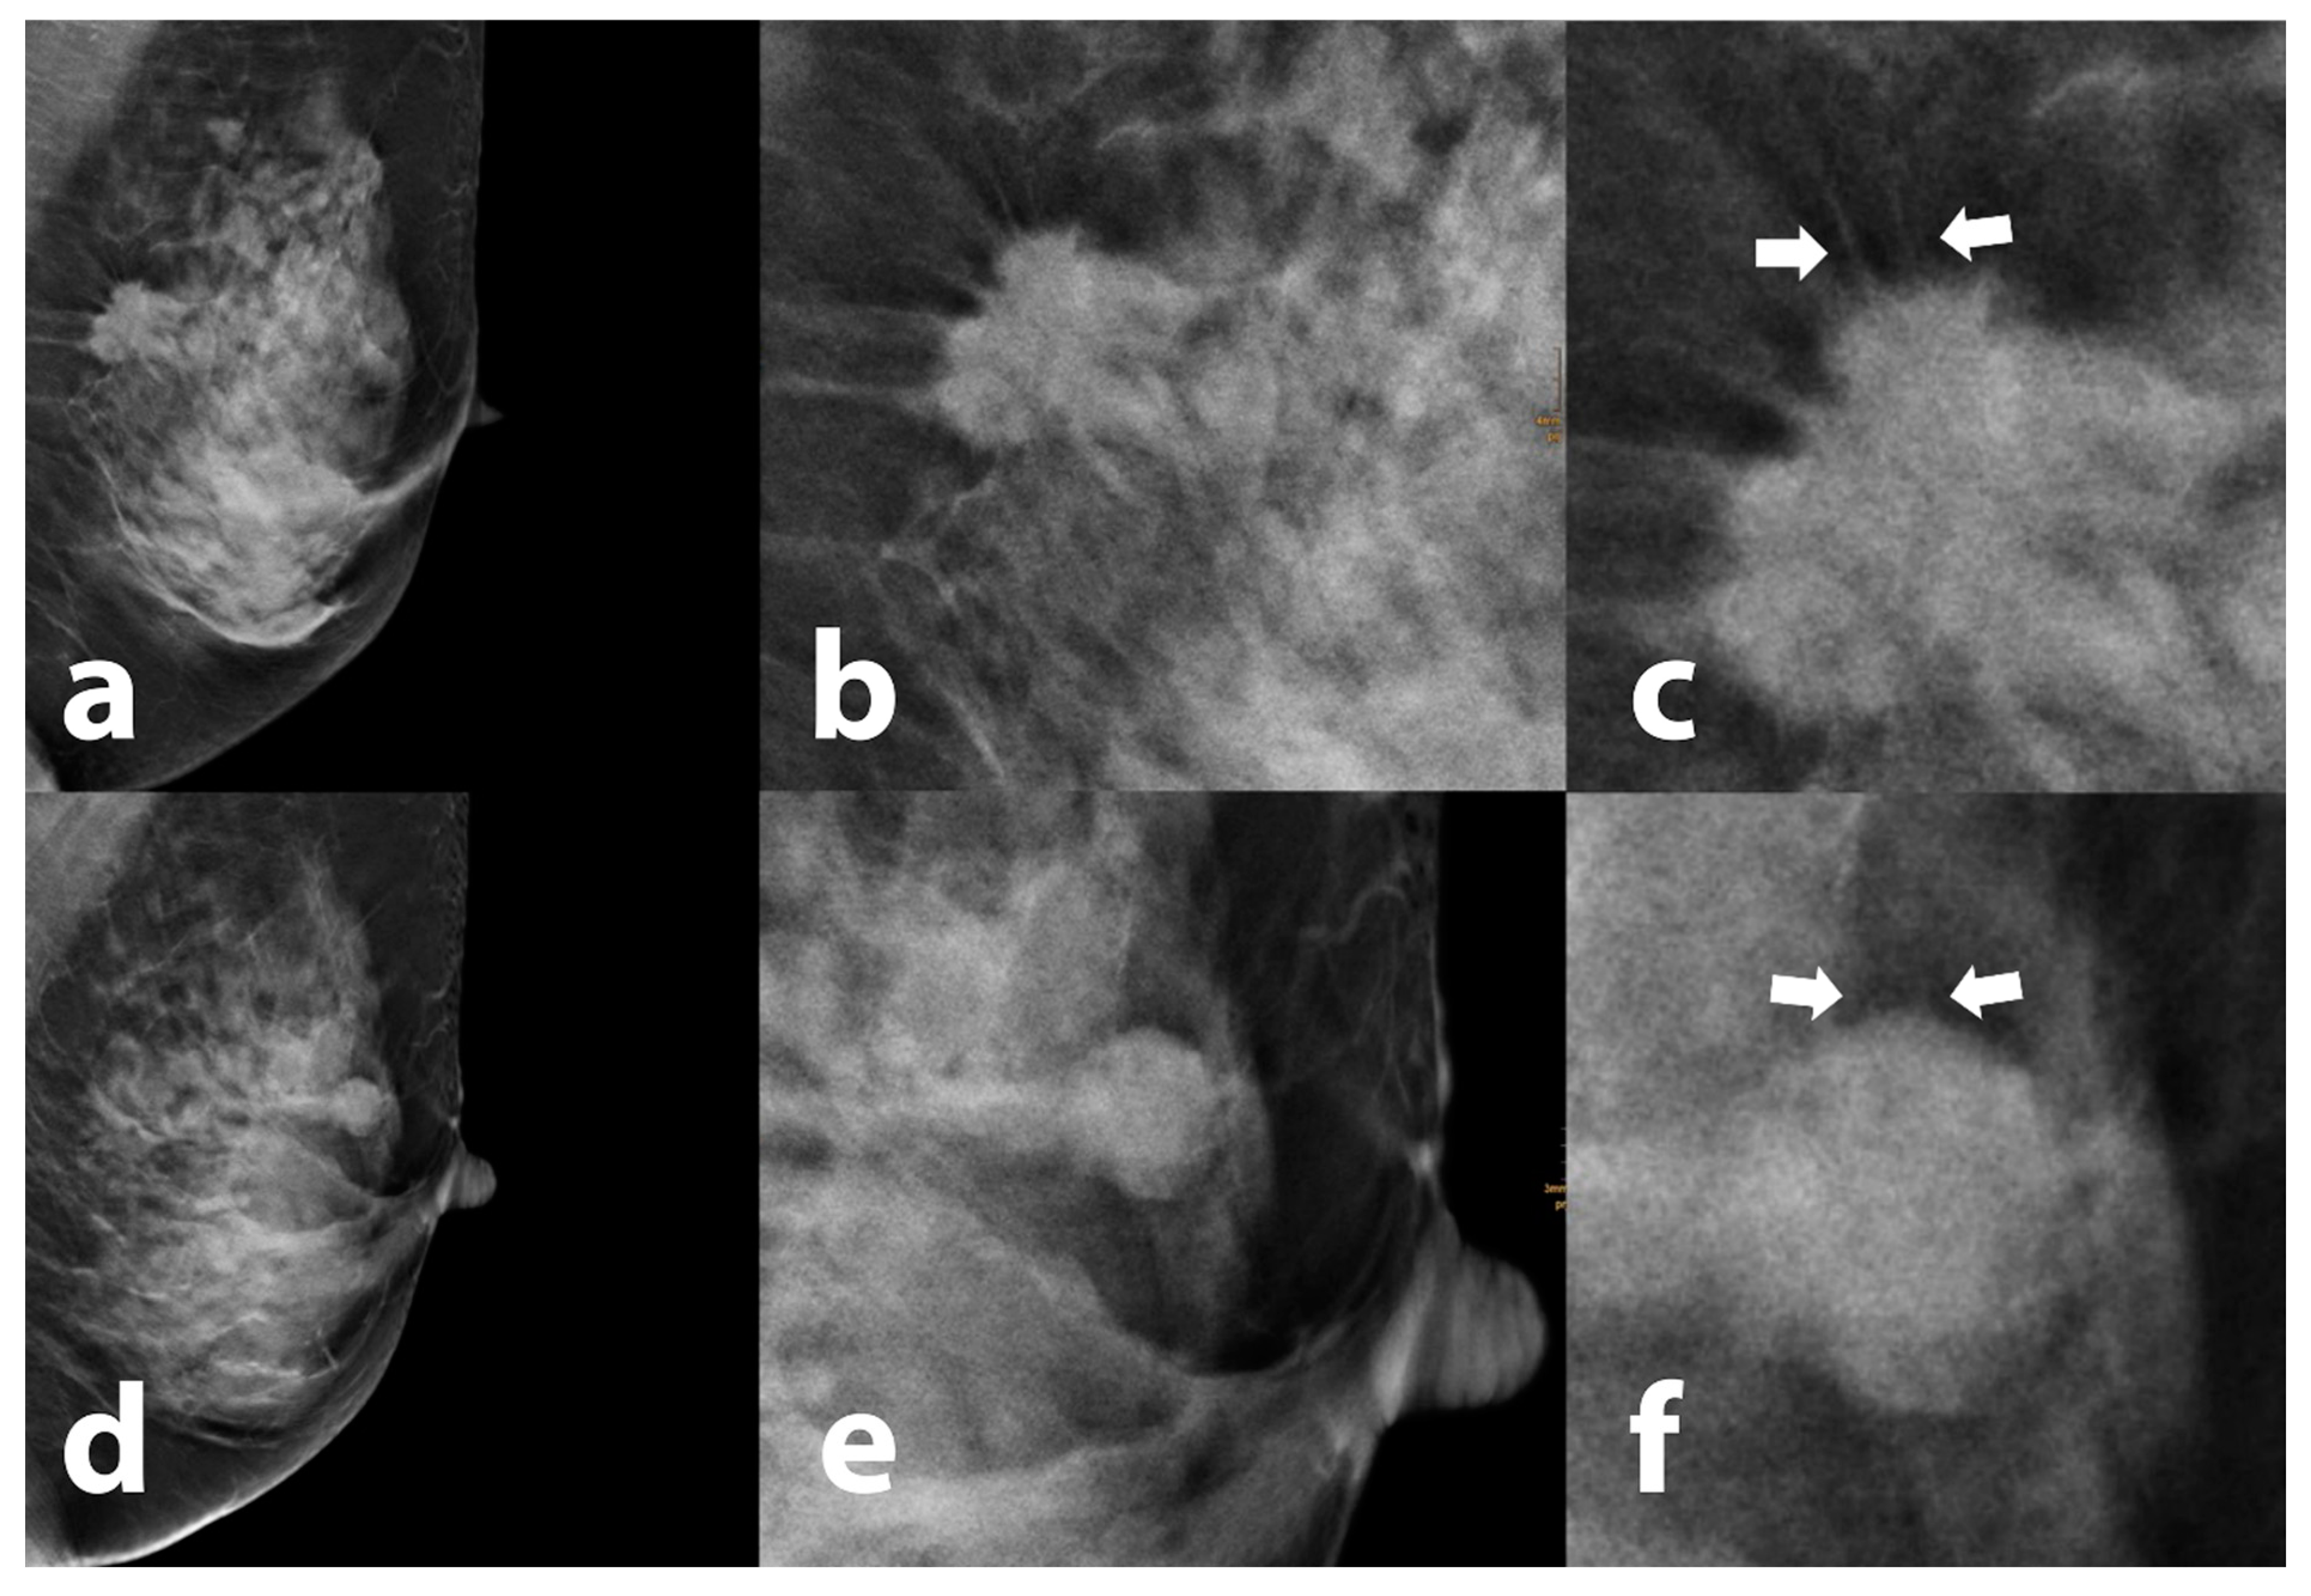

3.3. Tomosynthesis Evaluation